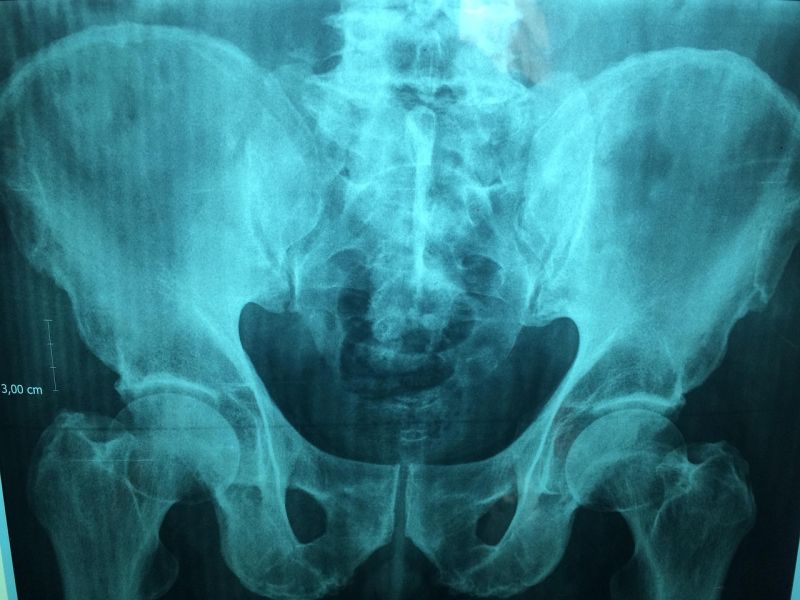

MSCT snimanje karliceMSCT snimanje karlice

Balkan Medic obavlja dijagnostiku putem usluge multislajsni CT skener karlice, koja omogućava detaljan uvid u stanje karličnih organa i kostiju.

Multislajsni CT skener karlice omogućava detaljno snimanje prostora između kukova, gde se nalaze mokraćna bešika, polni organi, limfni čvorovi, delovi creva i koštane strukture karlice. Snimanje se obavlja pomoću rendgenskih zraka i savremene računalne obrade, pri čemu se dobijaju precizni preseci u tankim slojevima. Ovakav prikaz pomaže da se promene jasno uoče i pravilno procene.

Zahvaljujući visokoj rezoluciji snimaka, multislajsni CT skener karlice omogućava uočavanje različitih stanja. Pregledom se mogu registrovati:

• tumori i druge izrasline u karličnoj duplji

• upale i infekcije mekih tkiva

• krvarenja i nakupljanje tečnosti

• kamenčići u mokraćnim putevima

• oštećenja i prelomi karličnih kostiju